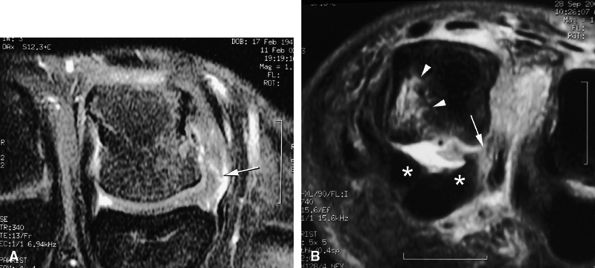

Intravenous injection of gadolinium may increase image contrast, making it possible to visualize small ligament tears (Fig. 11.13).10 Tears may involve the distal or proximal insertion or the middle third of the ligament (Figs. 11.13 and Fig. 11.14).

-

FIGURE 11.14 ● Collateral ligament tear of the metacarpophalangeal joint. Axial post-contrast fat-suppressed T1-weighted images with flexion of the joint. (A) Tear of the middle third of the ligament (arrow). (B) Distal tear (arrow) with a slight tilt of the volar plate (asterisks). There is associated contralateral bone edema of the metacarpal head (arrowhead).

|